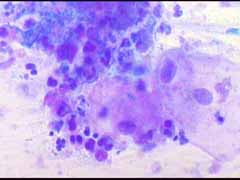

Ατυπα κύτταρα ενδοτραχήλου, άμεση χρώση με bleu de methylen 0,25% μεγεθ. 10Χ40. Αδενοκαρκίνωμα ενδοτραχήλου - ενδομητρίου